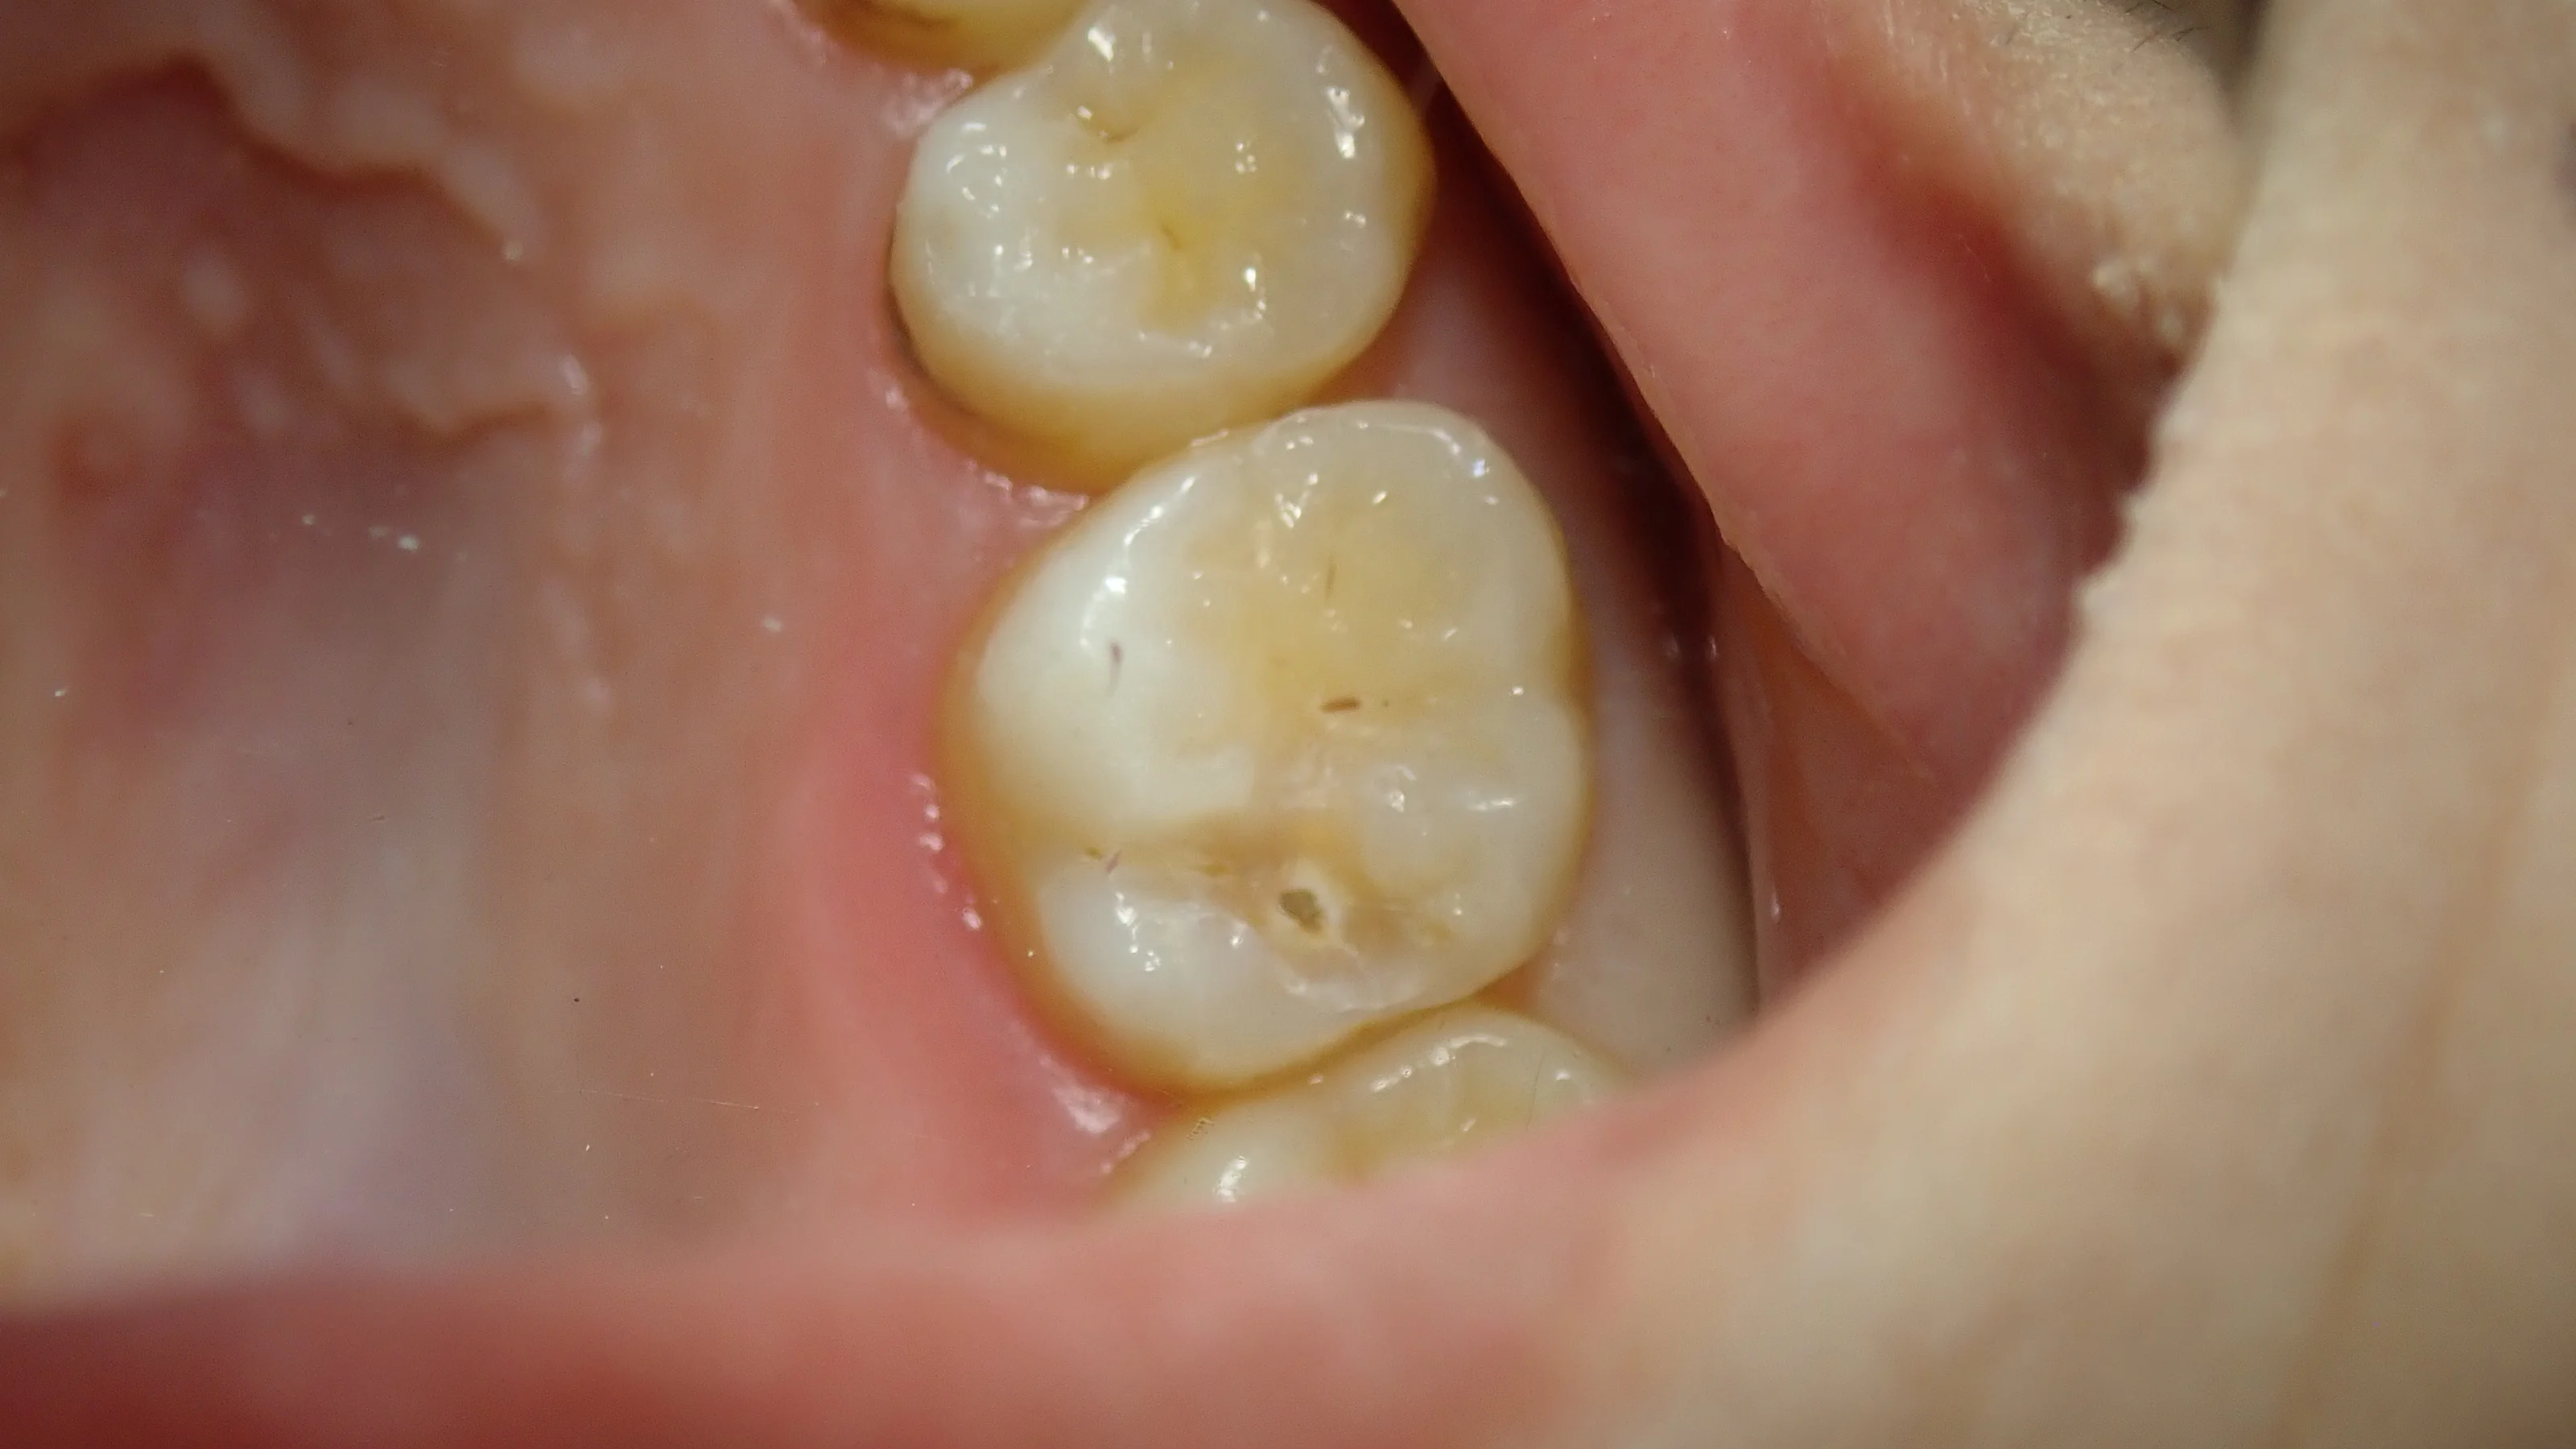

レジンを除去しきった状態ですが・・・

あからさまに穴が開いています。